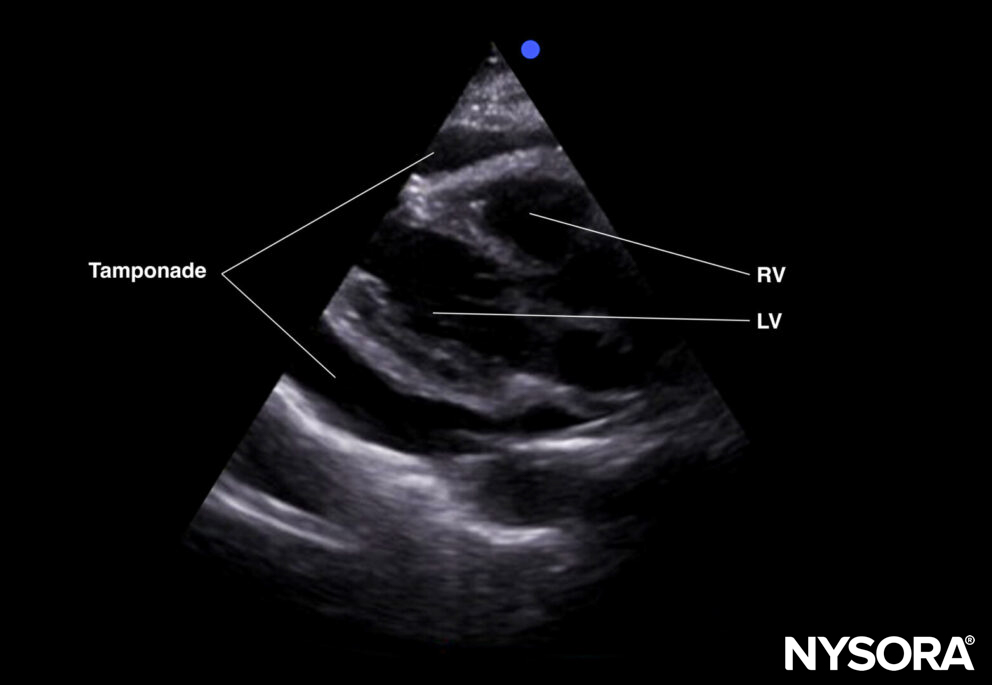

- Compression of the right atrium and right ventricle during diastole: more likely to result in tamponade.

Tamponade (parasternal short-axis view).

Tamponade (parasternal long-axis view).